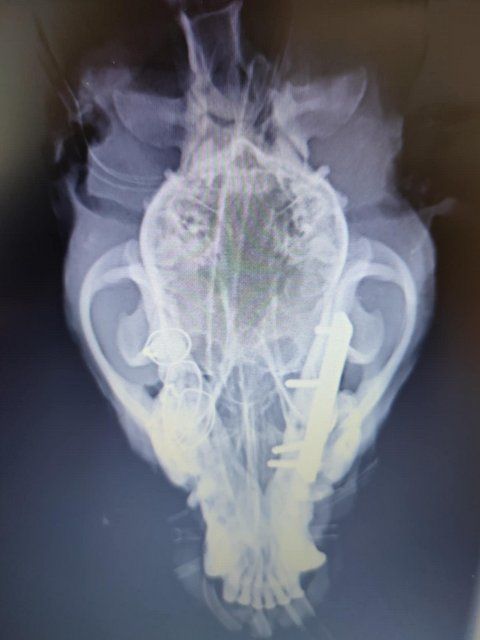

Röntgenbilder zeigten das Ausmaß der Zerstörung des Unterkiefers und den Bruch eines Beines.

Dieser Hund muss grausame Schmerzen haben, Zähne sind aus der Verankerung gerissen und sein Gesichtsschädel ist nicht mehr symmetrisch. Ein großes Stück des Unterkiefers ist komplett abgebrochen.

Camush Kopf ist wieder symmetrisch, der Kiefer wird jetzt mit Platte und Verdrahtung zusammengehalten und ein paar Zähne fehlen jetzt.

Sein Beinbruch ist ein offener Unterarmbruch von Elle und Speiche, der noch nach Erstversorgung operiert werden muss.